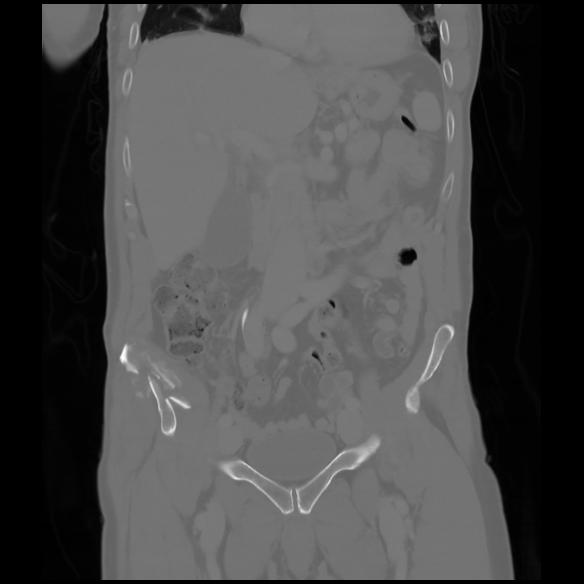

6 CUERPO,CE,Coronal,3.000,CUERPO,Coronal,